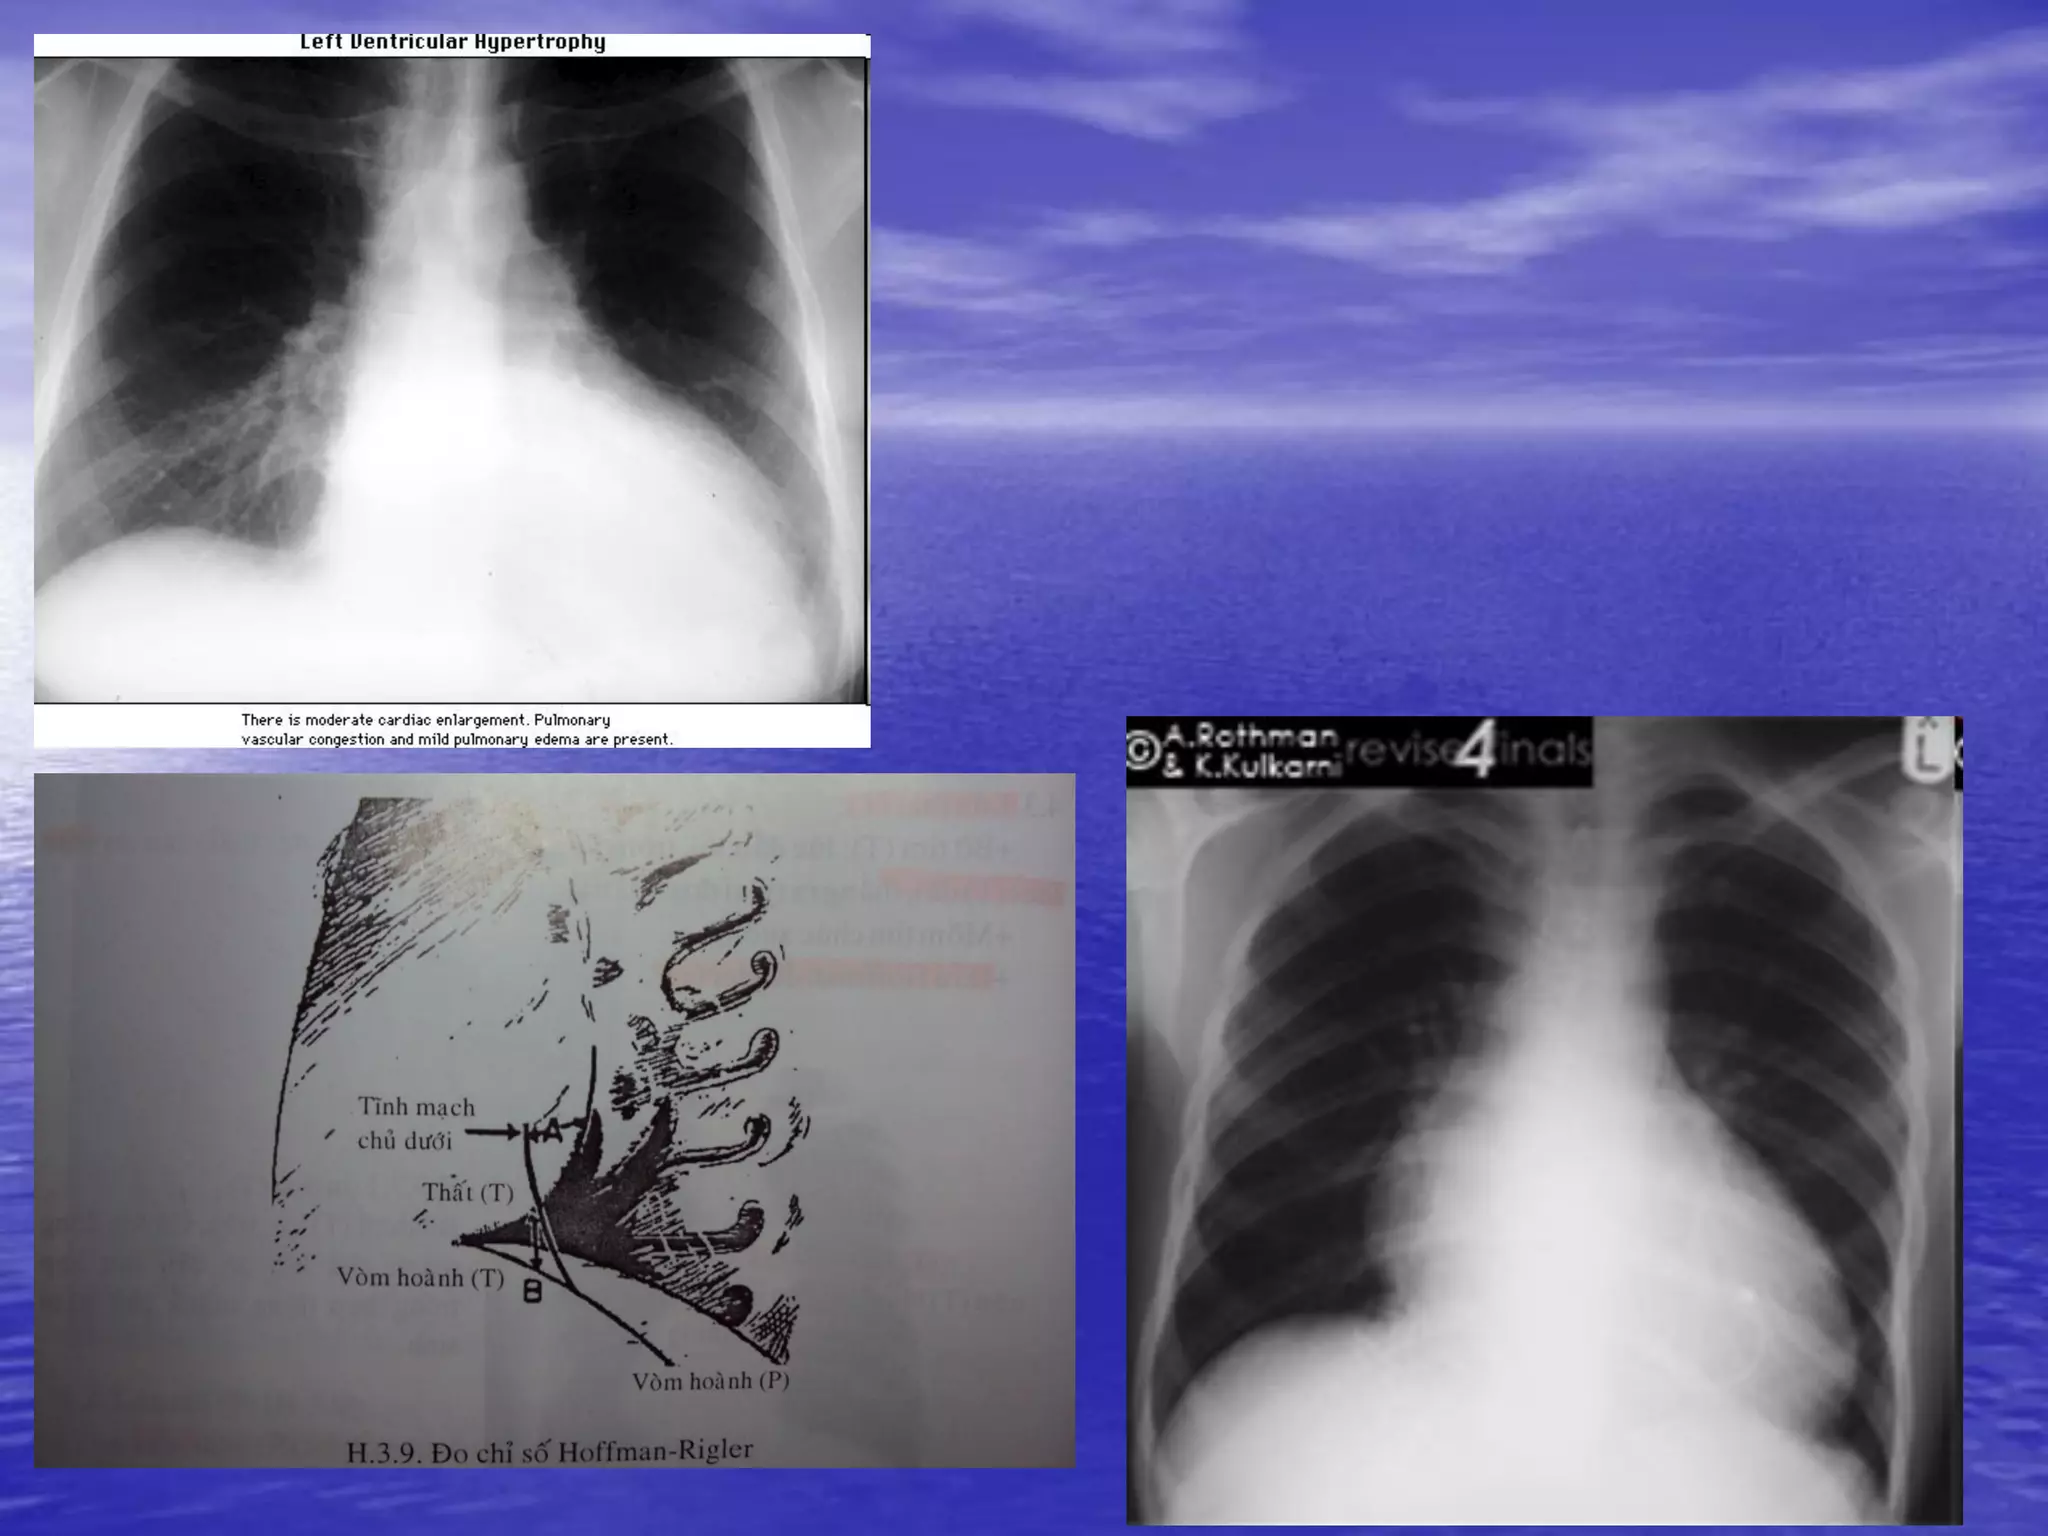

• Tiêu chuẩn đánh giá sự dãn lớn của tim và

các buồng tim

– Các buồng tim

• Tâm nhĩ T

– Bóng đôi ở bờ P tim

– 4 cung ở bờ T tim

– Góc Carena 70o

– TQ bị đẩy qua P và ứ đọng baryte phía trên/XQ nghiêng

• Tâm thất T

– Phì đại thất T

– Dãn thất T